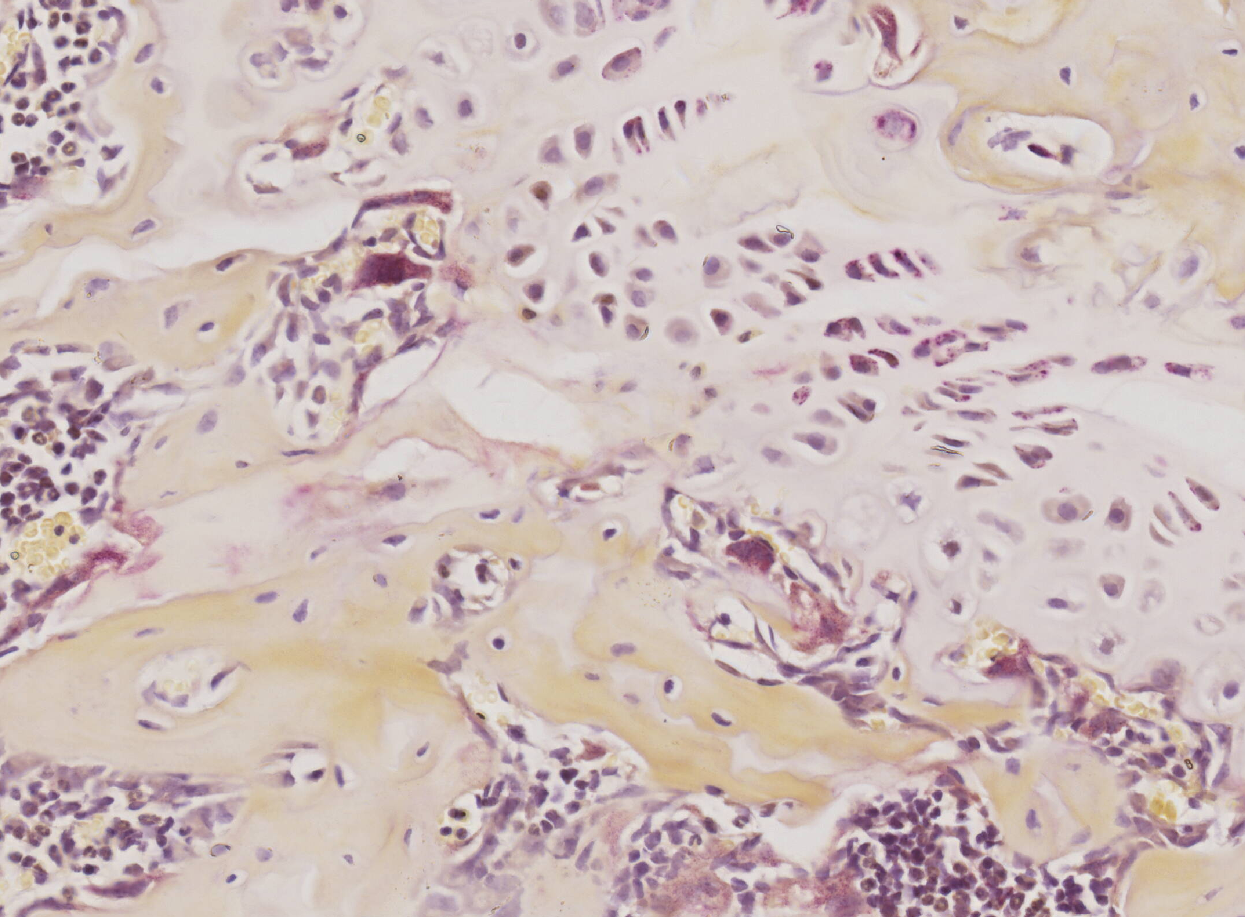

TRAP染色

骨关节 TRAP染色(示 破骨细胞)